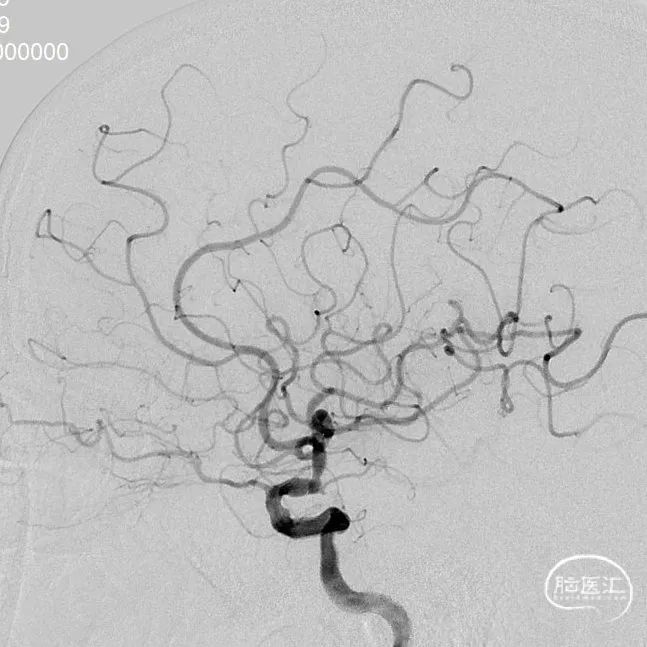

DSA示:左侧颈内动脉C7段重度狭窄(85%)以上。

2.0-9mm 颅内球囊扩张导管经交换导丝导引下至颈内动脉末端狭窄处,8atm(扩张时间240s)和10atm(扩张时间320s)大气压各球扩1次,手推造影示:远端血流改善明显,大脑中动脉窄程度减轻至30%。

2.25-9mm 颅内球囊扩张导管经交换导丝导引下至颈内动脉未端快窄处,6atm(扩张时间180s)和7atm(扩张时间230s)大气压各球扩1次,手推造影示:远端血流改善明显,大脑中动脉狭窄程度减经至10%。

赛诺神畅 3.5-15mm COMETIU™自膨式颅内药物涂层支架系统经交换导丝输送至狭窄远端,由远及近缓慢释放支架,支架完全覆盖狭窄段,造影示:颈内动脉末端狭窄基本纠正,远端血流良好。

10分钟后复查造影提示:颈内动脉末端狭窄基本纠正,远端血流良好。试验器械成功植入目标病变血管部位,输送系统成功,系统成功回撤,器械操作成功。

术后6个月随访:

2023-05-29复查脑血管造影示:左侧颈内动脉后交通段狭窄支架术后,支架在位,未见再狭窄。

术后18个月随访:

2024-06-28复查脑血管造影示:左侧颈内动脉后交通段狭窄支架术后,支架在位,形态良好,未见再狭窄。

术后24个月随访:

复查脑血管造影示:左侧颈内动脉后交通段狭窄支架术后,形态良好,未见再狭窄。

治疗后随访影像对比:

2022-11-30

COMETIU自膨式颅内药物涂层支架 3.5-15mm(侧位)

2024-06-28 18M-FU

(侧位)